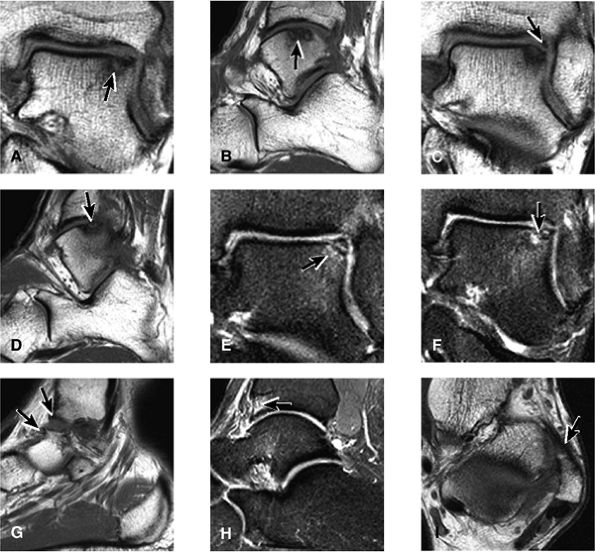

FIGURE 5.25 ● Sagittal anatomy of the ankle and foot. (A) The origins of the anterior talofibular ligament and posterior talofibular ligament are identified arising from the anterior and posterior distal tip of the lateral malleolus. From the origin, the full course of these ligaments can be followed medially on successive sagittal images to their insertions on the anterior and posterior talus. (B) The vertical course of a long segment of the peroneus longus and brevis tendons is often visualized on a single sagittal image through the tendons. This image is useful to further characterize tendinosis and longitudinal tears or splits, and for measuring the gap between completely ruptured tendon fragments. (C) The anterior process of the calcaneus is a common location for fractures that are occult on plain film. They are optimally visualized in the sagittal plane on MR exams. (D) In addition to occurring at the tibiotalar joint, degenerative arthrosis is also commonly found at the posterior subtalar, calcaneocuboid, and talonavicular joints. The cartilage surfaces and subchondral bone at these articulations are optimally visualized in the sagittal plane. (E) The presence of an os trigonum posterior to the talus predisposes certain athletes with a predilection for plantarflexion to the os trigonum syndrome. This is diagnosed on sagittal MR images when edema is visualized within the os trigonum and extends across the synchondrosis into the posterior talus. (F) Abnormal signal in the sinus tarsi manifests as high signal on FS fluid-weighted sequences and low signal on non-FS sequences. This abnormal signal may suggest, but is not specific for, inflammation in the sinus tarsi. Other causes of abnormal signal in the sinus tarsi, which may be incidental and asymptomatic, include extension of joint fluid from the posterior and middle subtalar joints, extension of generalized edema throughout the soft tissues of the ankle from stasis or other causes, enlarged vessels, and ganglion cysts.(G) Two potential causes of an incidental “mass” palpated on physical examination about the Achilles tendon are a low-lying soleus muscle and an accessory soleus muscle, both of which are diagnosed by MR imaging. The normal soleus muscle extends to about the proximal one third or one half of the Achilles tendon. A low-lying soleus will extend to the distal third of the tendon. An accessory soleus is present when there is an extra muscle in the pre-Achilles fat, usually extending to the distal third of the tendon, often near the distal insertion. (H) In the setting of a complete Achilles tendon rupture, the location of the tear may be at the myotendinous junction, mid-tendon, distal tendon, or tendon insertion at the os calcis. In addition, the tear is characterized as transverse or oblique longitudinal. In the case of transverse tears, the distance between the tear and tendinous insertion at the calcaneus is measured. Also, the length of good-quality tendon stump at the calcaneal insertion is measured, since the surgeon often uses the distal stump in the surgical reconstruction or repair. (I) The anteromedial aspect of the tibiotalar joint is a common location for the formation of large osteophytes, which extend anteriorly from the anteromedial tibia and talus. These may cause pain, limit the range of motion, or break off and form loose bodies within the tibiotalar joint. This spectrum of findings is part of the anteromedial impingement syndrome. (J) Ancillary findings at the plantar aponeurosis visualized on sagittal images include bone marrow edema within the inferior calcaneus, inferior calcaneal enthesophyte with marrow edema, and high signal within the flexor digitorum brevis muscle and fat that surround the plantar aponeurosis. These findings suggest active inflammation in the tissues surrounding the plantar aponeurosis. (K) The deltoid ligament is found on sagittal images by finding its origin extending off the bilobed medial malleolus. The medial course of the deltoid ligament components is followed over the next two or three successive sagittal images. (L) The vertical course of the tibialis posterior tendon and the flexor digitorum longus tendon is often visualized on a single image. Triangulating on tendon pathology in both the sagittal and axial planes aids in further characterizing tendon abnormalities.

FIGURE 5.26 ● Coronal anatomy of the ankle and foot. (A) The calcaneofibular ligament (CFL) is identified by finding its origin at the inferior tip of the lateral malleolus. The posterior inferomedial course of the CFL is followed on three or four consecutive coronal images moving posteriorly through the ankle, to its insertion on the posterolateral calcaneus. Optimal evaluation of the CFL involves examining its full course on successive images in both the coronal and sagittal plane for tears, sprain, or scarring. (B) The medial cord of the plantar aponeurosis is normally slightly thicker than the lateral cord, and this mild asymmetry in thickness should not be misinterpreted as plantar aponeurosis scarring or plantar fasciitis. On successive coronal images, the course of the plantar aponeurosis should be followed back to its insertion on the inferior calcaneus and evaluated for the presence of thickening, decreased signal suggestive of scarring, increased signal indicative of plantar fasciitis, and tears. (C) Coronal images are optimal for viewing the lateral process of the talus, which is a frequent site of fractures that are occult on plain films. Fractures of the lateral process of the talus are most common in patients with snowboarding injuries. (D) The talar dome and tibial plafond are optimally visualized on coronal images. They are assessed for the presence of subchondral edema and cystic change with overlying chondral abnormalities. Close attention should be directed to the extreme anterior and posterior margins of the cartilage-bearing articular surfaces of the talar dome and tibial plafond to avoid overlooking osteochondral lesions at these locations. (E) The origin of the anterior talofibular ligament (ATFL) is found at the anterior distal tip of the lateral malleolus, and the ATFL is followed anteriorly on two or three successive coronal images to its insertion at the anterior lateral margin of the talus. (F) The deltoid ligament is optimally visualized in the coronal and axial planes. Tears of the deltoid manifest as loss of fiber striation or diffuse amorphous hyperintensity in the ligament on fluid-weighted sequences. Partial tears are more common than complete tears. (G) Focal fatty atrophy and denervation of the plantar flexor muscles of the foot (abductor digiti minimi, flexor digitorum brevis, and abductor hallucis) may indicate neuropathy involving the tibial nerve or its branches. (H) At the level of the anterior aspect of the talus and calcaneus, the peroneal tendons and flexor tendons turn from their cranial—caudal course to travel an anterior-to-posterior course along the plantar aspect of the foot. The distal portions of the tendons should be examined along the plantar aspect of the foot on successive coronal images for evidence of tendinosis and tears. (I) The base of the fifth metatarsal is a common location for fractures and is often visualized within the FOV on ankle MR exams. (J) At the level of the navicular, the flexor digitorum longus (FDL) and flexor hallucis longus (FHL) tendons run side by side, with the FDL medial to the FHL. Anterior to this level on successive coronal images, the two tendons cross, with the FHL medial to the FDL as the FHL courses to its insertion on the great toe. (K) Stress fractures of the navicular are commonly vertical in the midline of the navicular, an appearance that is well characterized on coronal images. (L) Contusions, stress-related edema, fractures, and degenerative arthritis of the midfoot bones and joints are common causes of midfoot pain and are often optimally identified on fluid-sensitive sequences.

FIGURE 5.27 ● Axial anatomy of the ankle and foot. (A) The flexor digitorum longus, flexor hallucis longus, peroneus brevis, soleus, and extensor digitorum muscles are examined at this level for strain, tears, or fatty atrophy that may suggest denervation. (B) The tibialis anterior, extensor hallucis longus, and extensor digitorum longus tendons are examined on every ankle MR examination. Extensor tendon pathology is frequently overlooked if these tendons are not included as part of the ankle checklist. (C) Tears and sprains of the anterior syndesmotic ligament are a frequent cause of persistent ankle pain following ankle sprain. The syndesmotic ligaments are thick, tough ligaments that are important ankle stabilizers, and delayed diagnosis of syndesmotic tears may result in significant degenerative arthrosis at the tibiotalar joint due to the resulting ankle instability. The syndesmotic ligaments course obliquely inferiorly from the tibia to the fibula and are not usually visualized in their entirety on a single axial image; rather, their course is followed on at least two or three successive axial images. (D) The peripheral margin of the peroneal tendons and tibialis posterior tendon should normally never extend beyond the peripheral margins of the lateral and medial malleoli, respectively. Tendon subluxation around the posterior corner of either malleolus is indicative of a tear of the overlying flexor retinaculum (medially) or peroneal retinaculum (laterally). When the retinacula are torn, the tendon is free to intermittently sublux or dislocate, leading to tendon degeneration, pain, and tendon dysfunction. (E) Suspected osteochondral lesions of the talar dome are visualized and further characterized on axial images through the top of the talar dome. (F) The peroneus brevis tendon may normally appear somewhat flattened. However, as the tendon degenerates, it becomes U-shaped and drapes around the anterior aspect of the peroneus longus and becomes impinged between the peroneus longus tendon and the lateral malleolus. With further degeneration, the peroneus brevis may split or completely rupture. (G) Evidence of anterior talofibular ligament injury is visualized on the majority of MR ankle examinations and appears as thickening, intermediate signal with ill-defined fibers, or attenuation of the ligament. This is commonly asymptomatic. (H) Because the flexor hallucis longus tendon sheath communicates with the tibiotalar joint, fluid may normally be present within the tendon sheath in proportion to the amount of fluid in the tibiotalar joint. If there is fluid within the tendon sheath out of proportion to that seen in the tibiotalar joint, tenosynovitis is most likely present. The finding of flexor hallucis longus tenosynovitis should prompt a search for an os trigonum, as impingement of the flexor hallucis longus tendon between an os trigonum and the posterior tibial plafond is a common cause for FHL tenosynovitis. (I) The calcaneofibular ligament (CFL) passes anterior and medial to the peroneal tendons. On the image at which the CFL passes directly medial to the peroneus brevis tendon, the appearance of the peroneus brevis and the CFL side by side is occasionally mistaken for a split peroneus brevis tendon. (J) Dilated posterior tibial veins within the tarsal tunnel occasionally compresses the tibial nerve. In the setting of clinical suspicion for tarsal tunnel syndrome or if there is evidence of muscle denervation on MR images, the size of the posterior tibial veins should be described. (K) The spring ligament is identified at this axial image location, extending from the anteromedial calcaneus to the posteromedial navicular. Tears of the spring ligament may result in medial instability and hindfoot valgus. (L) The posterior tibialis tendon (PTT) may normally become thickened and fan-like as it passes posterior to its navicular insertion (prior to also inserting on the cuneiforms and the base of the second through fourth metatarsals). In the absence of other findings, the thickening of the PTT at this level should not be mistaken for focal tendinosis. (M) On inferior images through the ankle, Lisfranc's ligament is occasionally included in the FOV. Lisfranc's ligament extends from the medial cuneiform to the base of the second metatarsal. If Lisfranc's ligament is included in the FOV, the status of the ligament should be described, as undiagnosed Lisfranc ligament tears can lead to debilitating midfoot arthrosis. (N) As the medial and lateral tendons turn from their vertical course to a horizontal course along the plantar aspect of the foot, the tendons may demonstrate a magic-angle artifact, causing the tendons to appear gray on short-TE images, mimicking tendinosis. Correlation with images using longer TE values is advised in such situations.